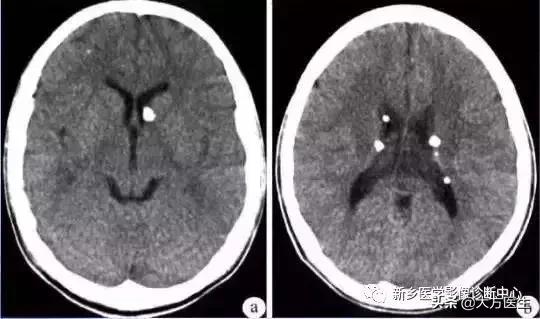

8、囊虫

常有生食猪肉史,癫痫、颅高压,皮下肌肉也可见囊虫结节。

多发钙化型:脑实质内多发小圆形钙化,无强化,囊性病变,壁 上有结节,长T1长T2信号。脑室型:多为脑室形状异常或局限性扩大。